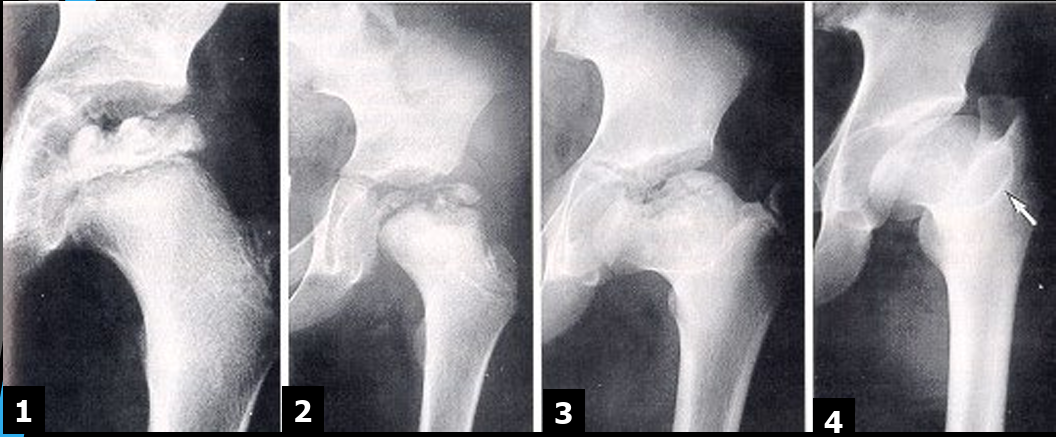

Early/Avascular

loss of blood supply to the FH leading to decrease in size

increased joint space, lateral femoral displacement

Fragmentation (of epiphyses)

crescent sign

blurred FH outlines

Repair

return of blood supply

new bone deposits

wide short femoral neck

Healed/Deformity

enlarged and flattened FH

enlarged GT